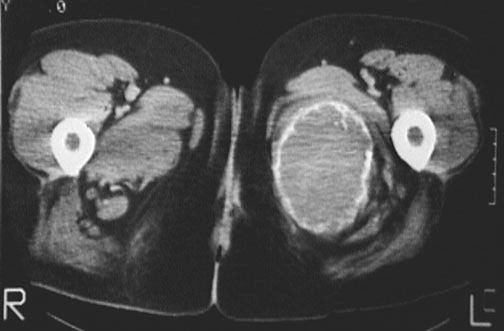

This is a giant cell tumor (GCT) of bone in the region of the upper thigh. This lesion arose in the left ischial ramus and demonstrates a thin sclerotic rim in axial view with this CT scan.